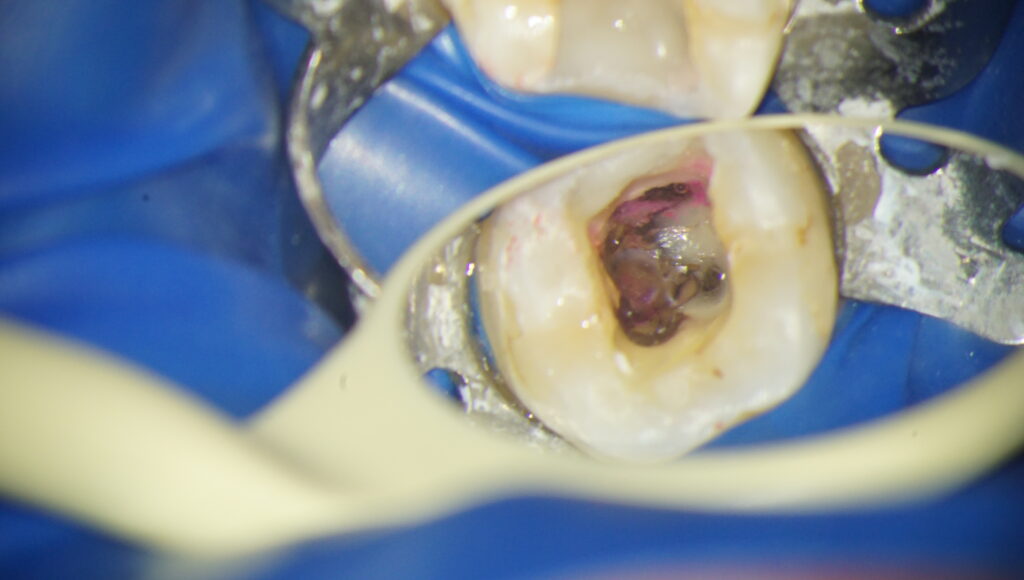

まさに今から抜髄を行う方です。

歯の内部を鏡で覗き込んでいます。

なんとなくきたない感じになっているのがお分かりいただけるかと思います。

大まかに神経と血管を除去した状態です。

さっきとは随分景色が違うのがお分かりいただけるかと思います。

文章で書くと2行ですが、1枚前の写真からこの写真に至るまで30分かかっています。

マイクロスコープを覗きながら、細かいところを処理していき、しっかり除去しきるためになかなか時間がかかるのです。